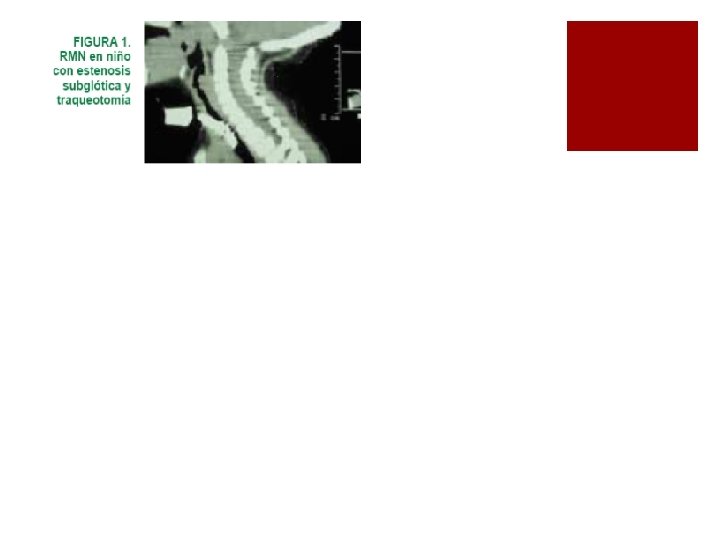

Diagnostico ¡Sospechar en niños con episodios gripales frecuentes con estridor dificultad respiratoria y tos seca ¡La auscultación laríngea permite identificar el estridor bifásico ¡la radiografía cervical PA y lateral blanda puede evidenciar la estenosis ¡Fibrolaringoscopia o una laringoscopia directa esencial para el dx. ¡TC Resonancia